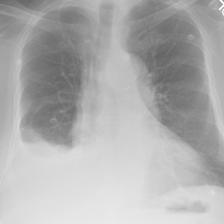

In this regard, VLP in biomedicine and radiology poses a distinctive challenge, as reports routinely include comparisons to prior imaging studies [47, 3, 57]. Without knowledge of this prior image111In the MIMIC-CXR v2 dataset [36], around 40% of reports explicitly reference a previous image. See Appendix B for details., temporal information in the text modality, e.g. “Pneumonia is improving”, could pertain to any image containing “Pneumonia”, producing ambiguity during contrastive training (Figure 1). Despite this, the existing VLP work to date considers alignment between only single images and reports [81, 32, 46, 9], going so far as to remove temporal content from reports in training data to prevent ‘hallucinations’ in downstream report generation[54]. However, temporal information can provide complementary self-supervision, solely by exploiting existing structure, and without requiring any additional data.

In Figure A.3, we show examples of self-attention rollout [1] maps for pleural effusion and consolidation, including radiologist-annotated bounding boxes surrounding the corresponding pathology in each prior and current image.

To model the attention flow through the transformer encoder block, we first average each attention weight matrix across all heads, subsequently we multiply the matrices between every two layers. For every block we add the identity matrix in order to model the residual connections. Last, we only keep the top 10 of attention weights per block to reduce noise in the final rollout map. In contrast to [21], we do not visualize the rollout map with respect to a [CLS] token. Instead, we choose a reference image patch from the center of the radiologist-annotated bounding boxes, marked with in Figure A.3.

We find that the rollout maps in Figure A.3 are in good agreement with radiologist-annotated bounding boxes, i.e., the reference patch attends to other patches within the bounding boxes in the prior and current image. In addition, we find that BioViL-T is robust to pose variations, e.g., in Figure A.3 (a) we show that despite the vertical shift between prior and current image, the reference patch attends to the correct image patches in the prior image.